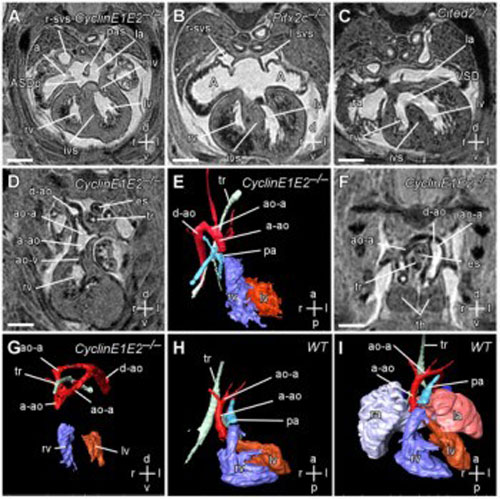

Due problemi principali influenzano lo sviluppo del cuore dell’embrione: non è un processo semplice ed è facile che si verifichino errori. Alcuni scienziati in Germania potrebbero essere riusciti a risolvere il mistero del perché i bambini possono nascere con difetti cardiaci congeniti. I ricercatori dell’istituto Max Planck di ricerca cardio-polmonare hanno scoperto una molecola che aiuta a regolare la funzione delle cellule staminali del cuore. Le loro scoperte potrebbero aiutare i ricercatori a contenere il numero di difetti cardiaci in futuro ma potrebbero anche portare a nuovi metodi per stimolare la rigenerazione dei cuori danneggiati negli adulti.

Il processo per andare dal punto A al punto Z nello sviluppo di un cuore è lungo. Le cellule si dividono e si trasformano in una raccolta di appena un paio di cellule staminali cardiache e poi in una struttura più grande dalla quale si sviluppa il cuore e che comprende gli atri, i ventricoli, le valvole e i vasi coronarici.

Praticamente le cellule staminali e i precursori passano attraverso un processo complesso che comprende una divisione cellulare regolata, la migrazione, la differenziazione e la specializzazione delle cellule. Le cellule staminali si disattivano quando lo sviluppo del cuore è completo.